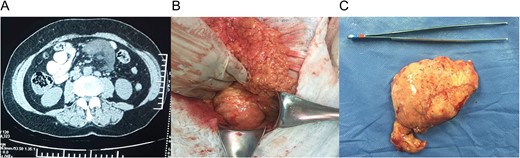

(A) Computed tomography (CT) with a 9 × 7 × 4 cm mass within the small bowel mesentery near the root of the mesentery. (B) Mass in the root of small bowel mesentery near the mesenteric vessels. (C) External surface of the mass.

With these findings, surgery was decided and at laparotomy, a 9, 5 × 7 × 5 cm3 mass was discovered in the root of small bowel mesentery, near but not in contact with major vessels, it was completely resected with a 0.5 cm margin, respecting bowel wall and vessels (Fig. 1B).